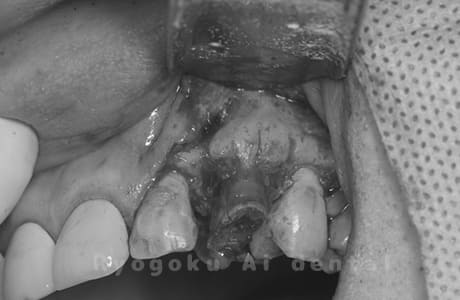

前歯の虫歯が大きく、3前歯部を含む歯周外科・クラウンレングスニングを行った患者様です。

<リスク・副作用>

手術後は痛み、腫れ、痺れ、青あざなどの副作用が生じます。痛みは痛み止めを処方しますが、腫れ、青あざは1週間程度生じる場合があります。また、部位によっては神経の走行が複雑で、痺れが残り、長期的にお薬を処方する場合があります。

Case01

-

- 原因

- 重度縁下カリエス

- 治療期間

- 約4ヶ月(最終補綴物装着まで含む)

- 治療内容

- クラウンレングスニング+歯周外科

- 治療費用

- 110,000円(最終補綴を除く)